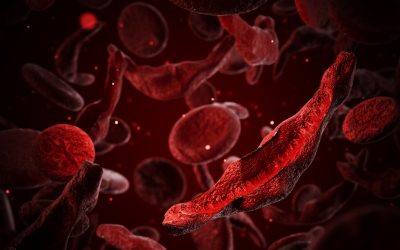

New pain-relief opioid could be much less addictive than morphine, rodent study finds

**New Opioid Candidate Shows Potential as Safer Pain Relief Alternative** A groundbreaking study in laboratory rats indicates that a newly developed synthetic opioid may offer a promising alternative to highly addictive pain medications such as morphine and fentanyl....

$3 million prize goes to duo whose research led to first sickle cell CRISPR therapy

Two pioneering scientists have been awarded the prestigious $3 million Breakthrough Prize in Life Sciences for their groundbreaking contributions that led to the development of the first approved therapy utilizing the revolutionary CRISPR gene-editing technology....